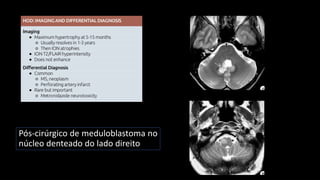

Degeneração olivar hipertrófica

Núcleo denteado

Triangulo de Guillain-Mollaret

Pós-cirúrgico de meduloblastoma no

núcleo denteado do lado direito

Infarto mesencéfalo

Núcleo denteado Núcleo denteado Núcleodenteado Triangulo de Guillain-Mollaret

Pós-cirúrgico de meduloblastomano núcleo denteado do lado direito